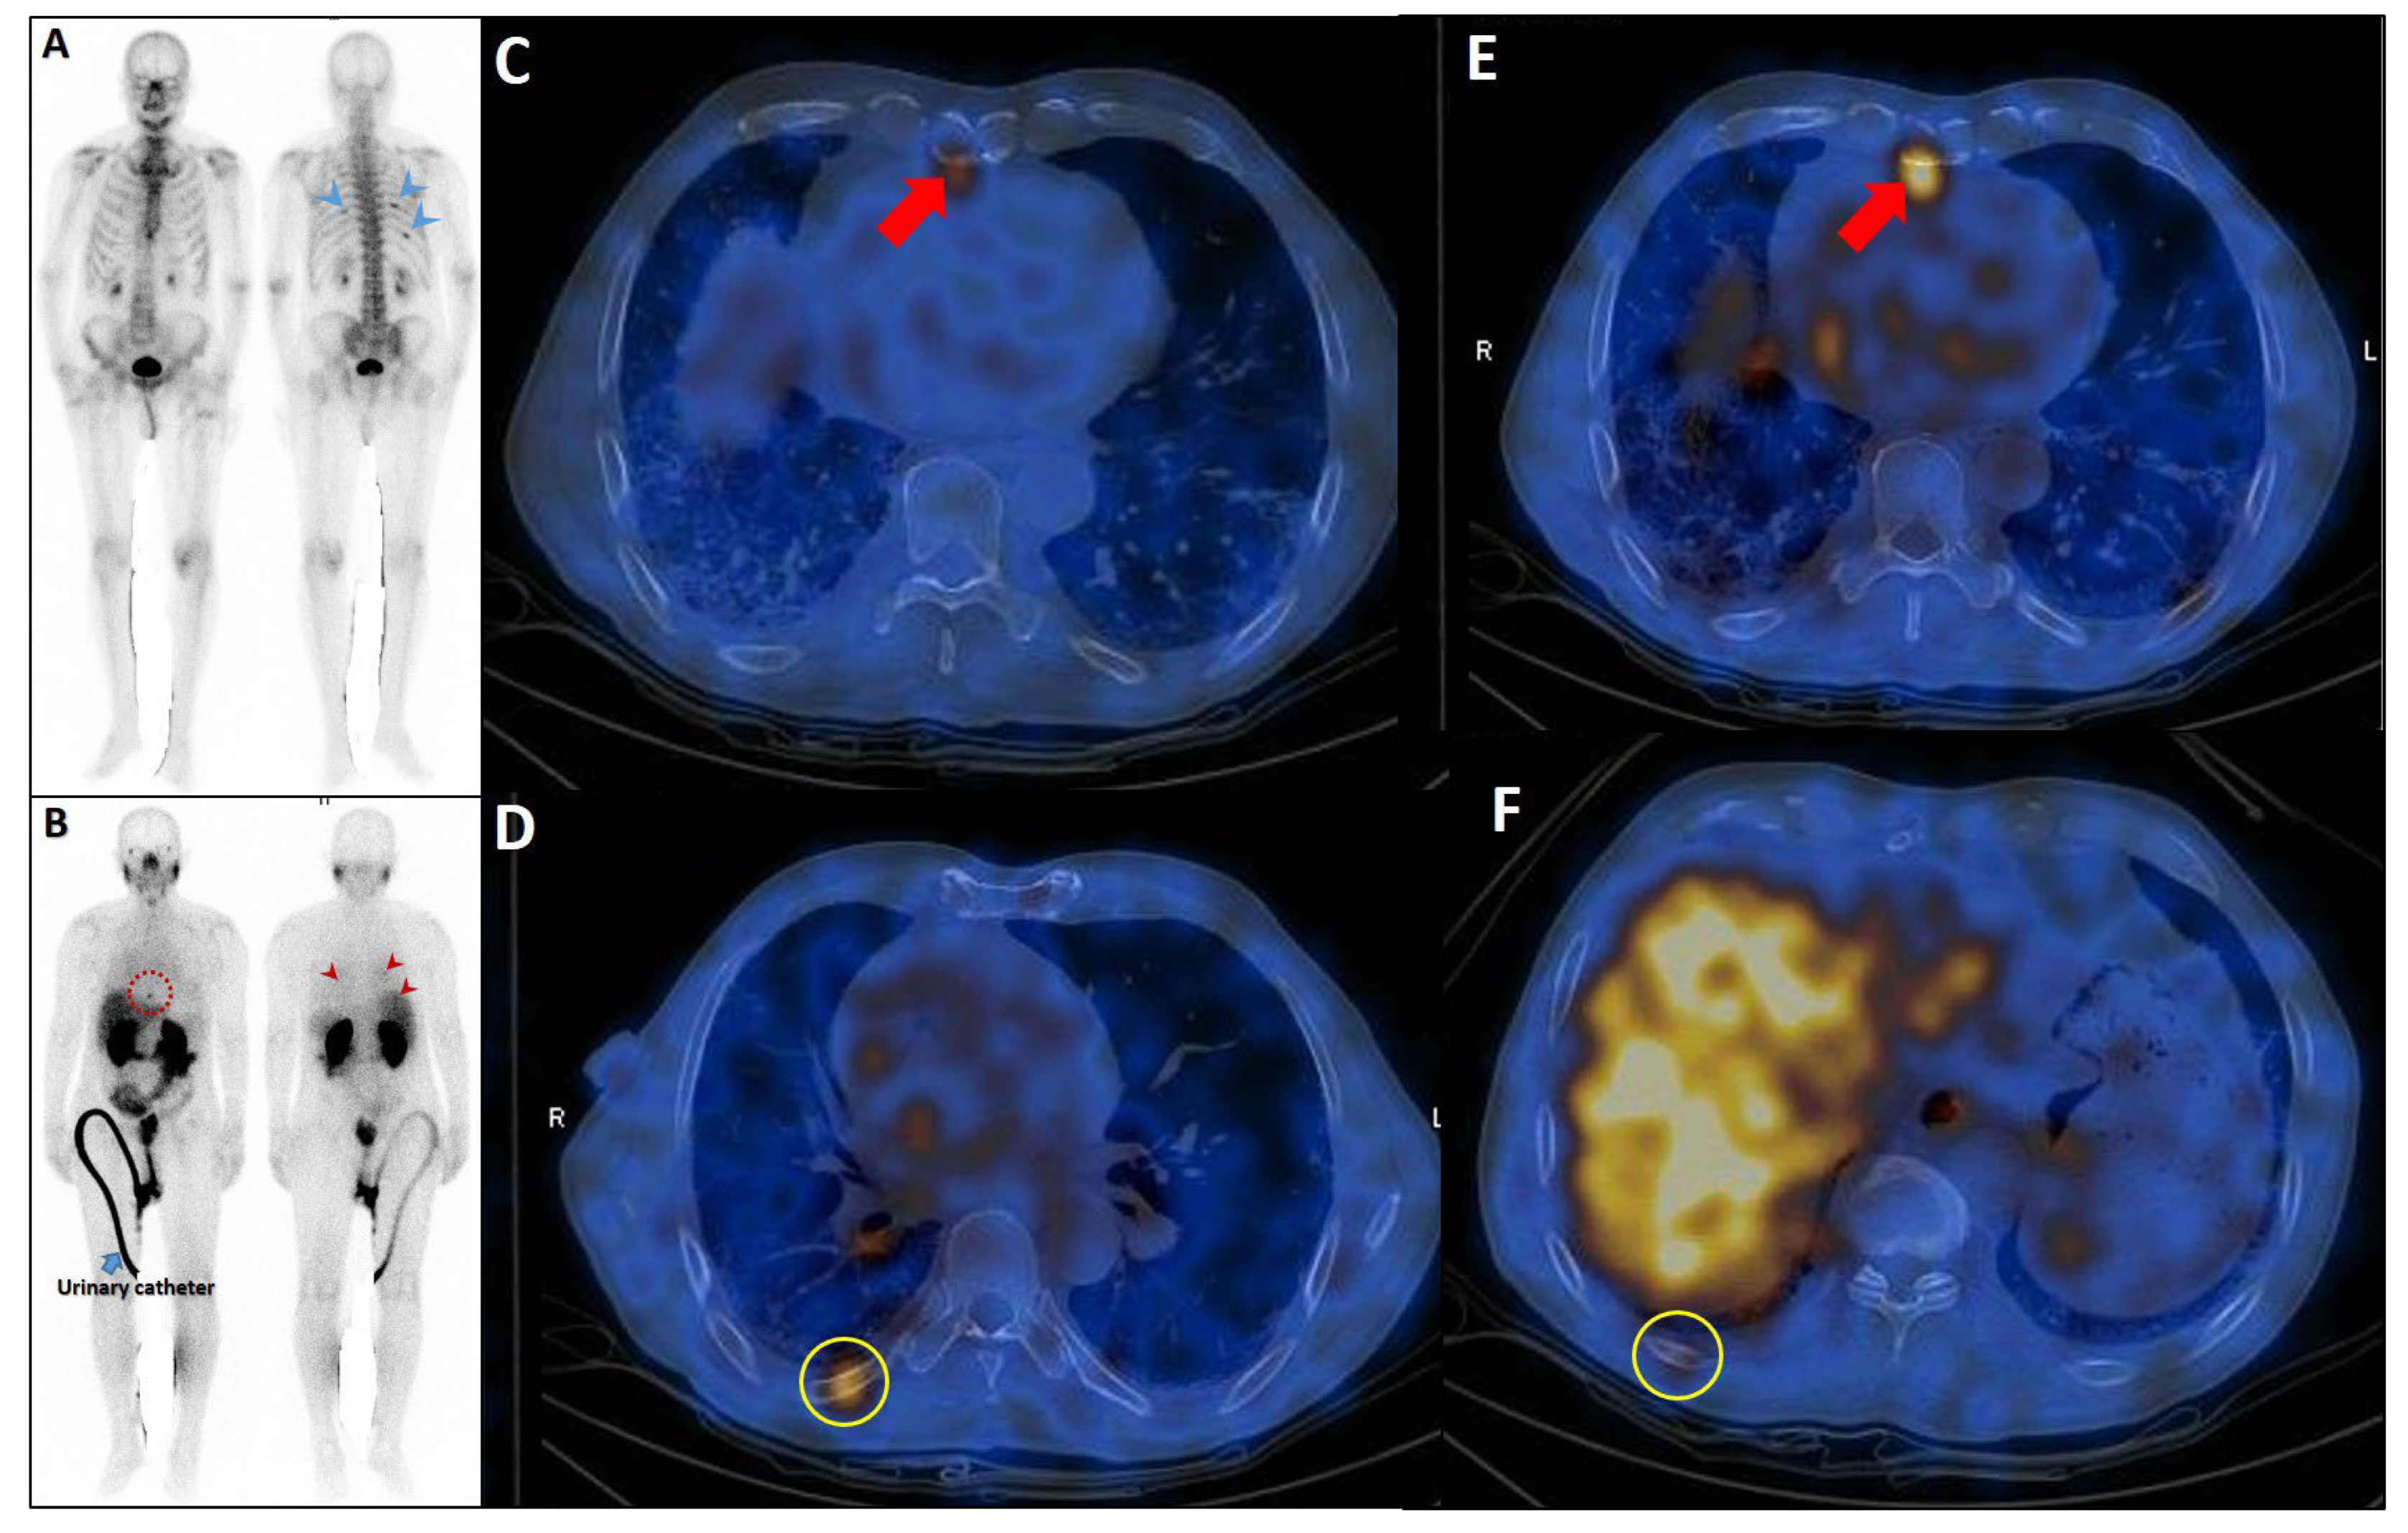

Figure 8.

Complementary role of PSMA SPECT/CT to bone scan in a patient with equivocal rib metastases. A very-high-risk prostate cancer patient (Gleason score: 5 + 4, serum PSA = 43 ng/dL) was referred for staging. The bone scan revealed at least three foci of osteoblastic activity in the ribs posteriorly ((A), blue arrowheads). Subsequently, the patient underwent PSMA SPECT/CT (B–F), confirming a mild PSMA avidity in the mentioned regions ((B), red arrowheads) with subtle sclerotic changes in two of them ((D,F), yellow circles). Moreover, another focus of uptake was noticed in the xiphoid process ((B), dashed red circle; (C,E), red arrows). Given the patient’s clinical history, presence of lymph nodes metastases (not shown), and possibility of xiphoid involvement, the patient was finally concluded as having metastatic rib lesions in the bones.